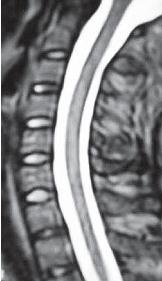

Как известно, шейный отдел позвоночника обильно снабжён сосудами, нервами. Пока позвоночник относительно «здоров» и имеет нормальный лордоз и «рабочее» состояние межпозвонковых дисков, то с сосудами, нервами, как правило, всё в порядке, то есть всё функционирует в естественном режиме. При прогрессировании дегенеративно-дистрофического процесса физиологический лордоз изменяется, что приводит к соответствующим проблемам. Для более предметного понимания сути вопроса предлагаю ознакомиться с рядом снимков МРТ шейного отдела позвоночника разных людей в качестве своеобразного визуального пособия и провести соответствующие самостоятельные сравнения состояния шейного отдела у данных пациентов.

Возьмём за вариант нормы данный снимок МРТ № 46, на котором наблюдается нормально выраженный лордоз, высота межпозвонковых дисков, ширина позвоночного канала. Самое главное — отсутствие стеноза (сужения).

Спинной мозг: контуры ровные, чёткие, структура гомогенная (греч. homogees — однородный), расположен почти в центре позвоночного канала и имеет нормальную толщину. Участков его патологического расширения или сужения не наблюдается. Ликворные пути свободны, проходимы.